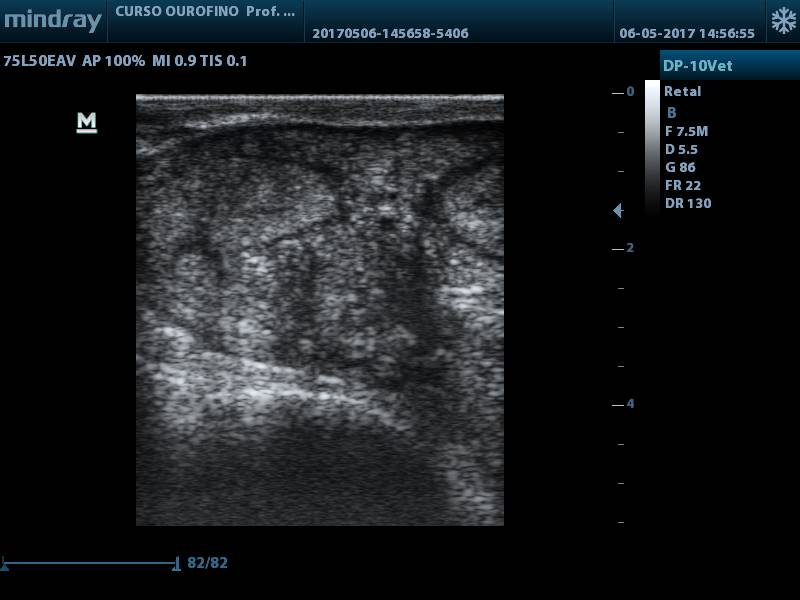

Após 30 dias pós-parto (D+30), durante exame de rotina realizado pelo médico-veterinário responsável, foi notado acúmulo de líquido no útero, palpação retal, porém, sem alteração dos parâmetros fisiológicos e hemograma dentro dos padrões esperados. No exame ultrassográfico foi confirmada a presença de substância com característica hiperecóica no lúmen uterino (fig. 1) e corpo lúteo (fig. 2).

Figura 1.